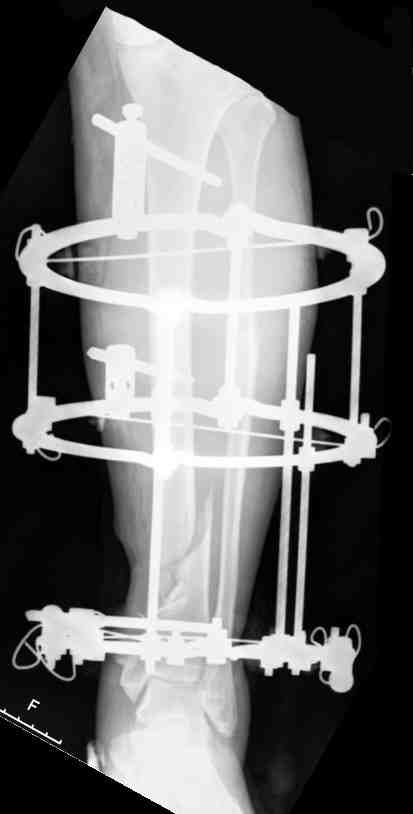

Выше представлены рентгенограммы открытого оскольчатого перелома нижней трети голени

X-rays of Compound Comminuted # Distal/3 Lt Tibia

Операционные снимки перед и после наложения аппарата Илизарова

In operation room before and after Ilizarov apparatus has been applied

Послеоперационные рентгенограммы

Postoperative X-rays

В нижнем ряду представлены рентгенограммы после окончательной репозиции.

And final reduction after Hexapod program has been finished